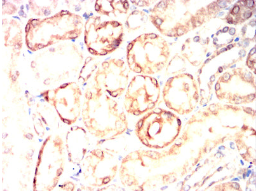

TPSAB1 Mouse Monoclonal antibody[6B611]

IHC    1/200 - 1/1000